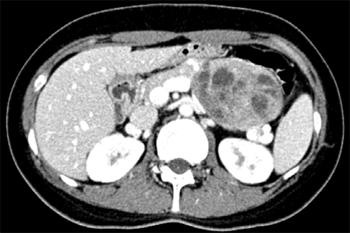

췌장의 낭종성 병변으로 판단하고 자세한 관찰과 필요한 경우 조직검사 혹은 세포흡인검사를 위하여 내시경초음파(EUS)를 시행하였다. 췌장 미부의 echogenic round mass가 관찰되었고 종괴 내부에는 다양한 크기의 낭성 병변이 동반되어 있었다. 낭내에는 격벽이나 벌집 (honeycomb) 양상, 석회나 벽결절 (mural nodule) 등은 관찰되지 않았다 (Fig. 2).

Figure 2. Round echogenic mass was noted on the tail of pancreas with multiple variable sized round small cystic lesions.